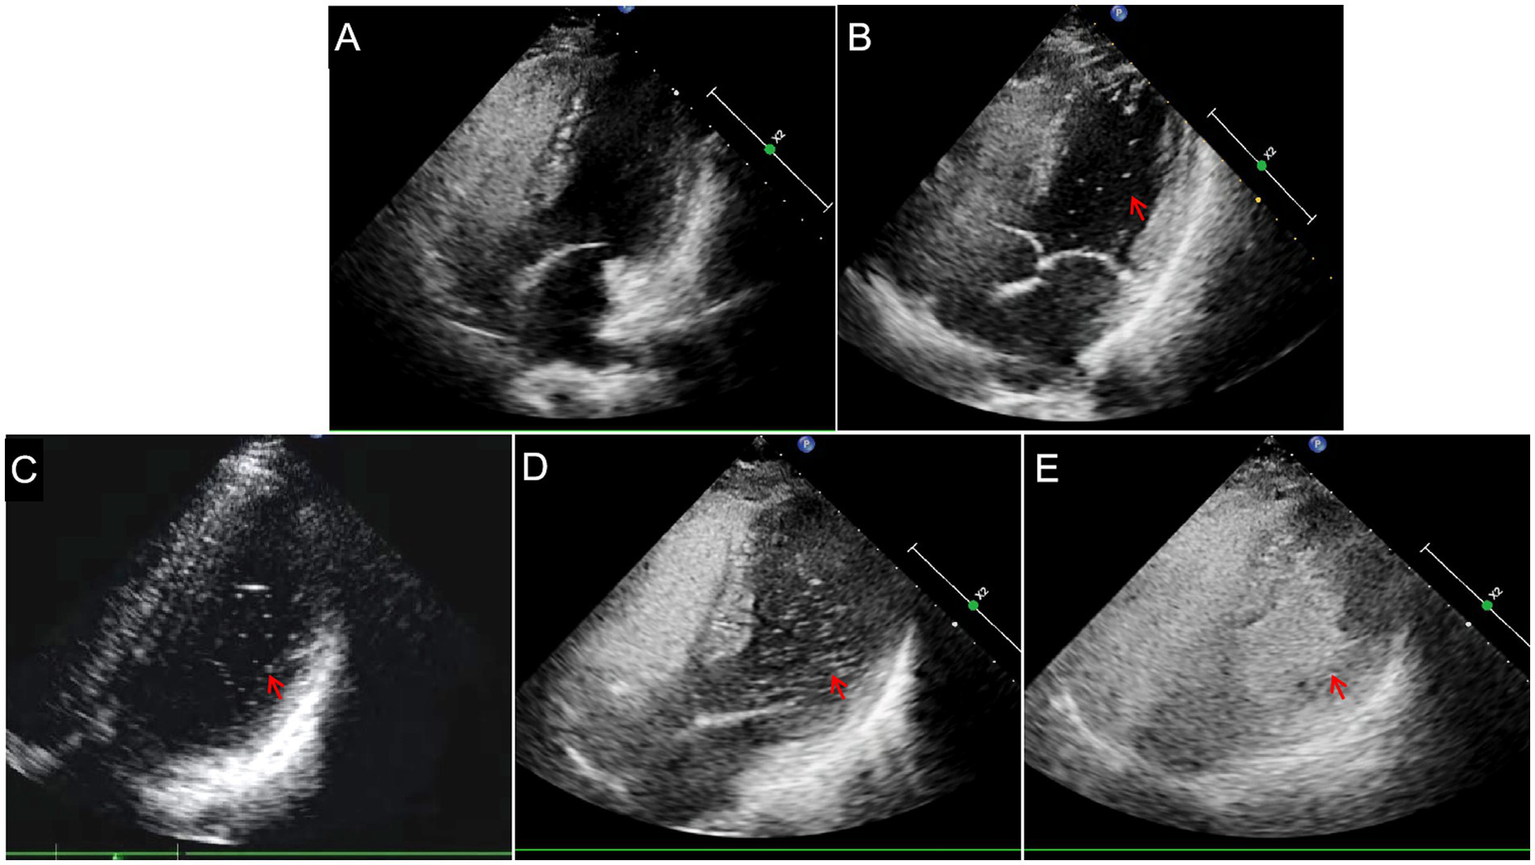

2.5. cTTE

cTTE was performed with an EPIQ 7C Color Doppler Ultrasound instrument (Philips, the Netherlands), with an X5-1 probe and a frequency of 1.0–5.0 MHz. We focused the ultrasound probe on the atrial septum and observed whether an interruption of echo continuity in the atrial septum and color blood flow through the interrupted site of the atrial septum were present. We recorded continuously during the contrast injections using the apical four-chamber view. When the TTE detected microbubbles in the left atrium within 5–7 cardiac cycles, the cTTE results were considered positive. The test in which the most microbubbles appeared in the left atrium was considered for the final result. The degree of shunt severity in cTTE based on the detected microbubbles in the left atrium was quantified as follows (6): grade 0 TTE (negative) = no microbubbles, grade I TTE = 1–10 microbubbles, grade II TTE = 11–30 microbubbles, and grade III TTE = more than 30 microbubbles (the left atrium is nearly filled with microbubbles or left atrial opacity is present; Figure 2).

Figure 2

Semi-quantitative grading of right-to-left shunts in contrast transthoracic echocardiography. (A) Grade 0TTE = negative. (B) Grade ITTE = 1–10 microbubbles (arrow). (C) Grade IITTE = 11–30 microbubbles (arrow). (D) Grade IIITTE = >30 microbubbles (arrow) or (E) the left atrium is nearly filled with microbubbles (arrow).